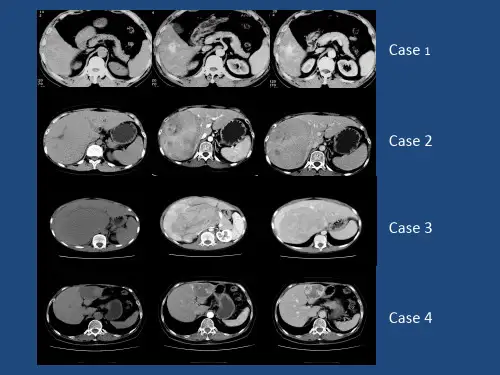

4、肝肿瘤肝肿瘤包括肝细胞肝癌、胆管细胞癌、肝内胆管细胞囊性腺瘤等。

在影像学上,肝肿瘤表现为肝内占位性病变,边缘不规则,可出现强化不均匀,同时可观察到肿瘤周围的肝组织改变。

不同类型的肝肿瘤还具有一些特殊的影像学表现,如肝细胞癌出现动脉期强化,胆管细胞癌可出现胆管扩张等。

4、肝癌肝癌是肝脏最常见的恶性肿瘤之一,其影像学表现多样化。

在超声检查中,肝癌通常呈现为低回声结节,有时伴有内部回声增强。

CT和MRI可显示肝癌的形态、分布和浸润范围,包括血供情况、肿瘤毛刺和转移灶。